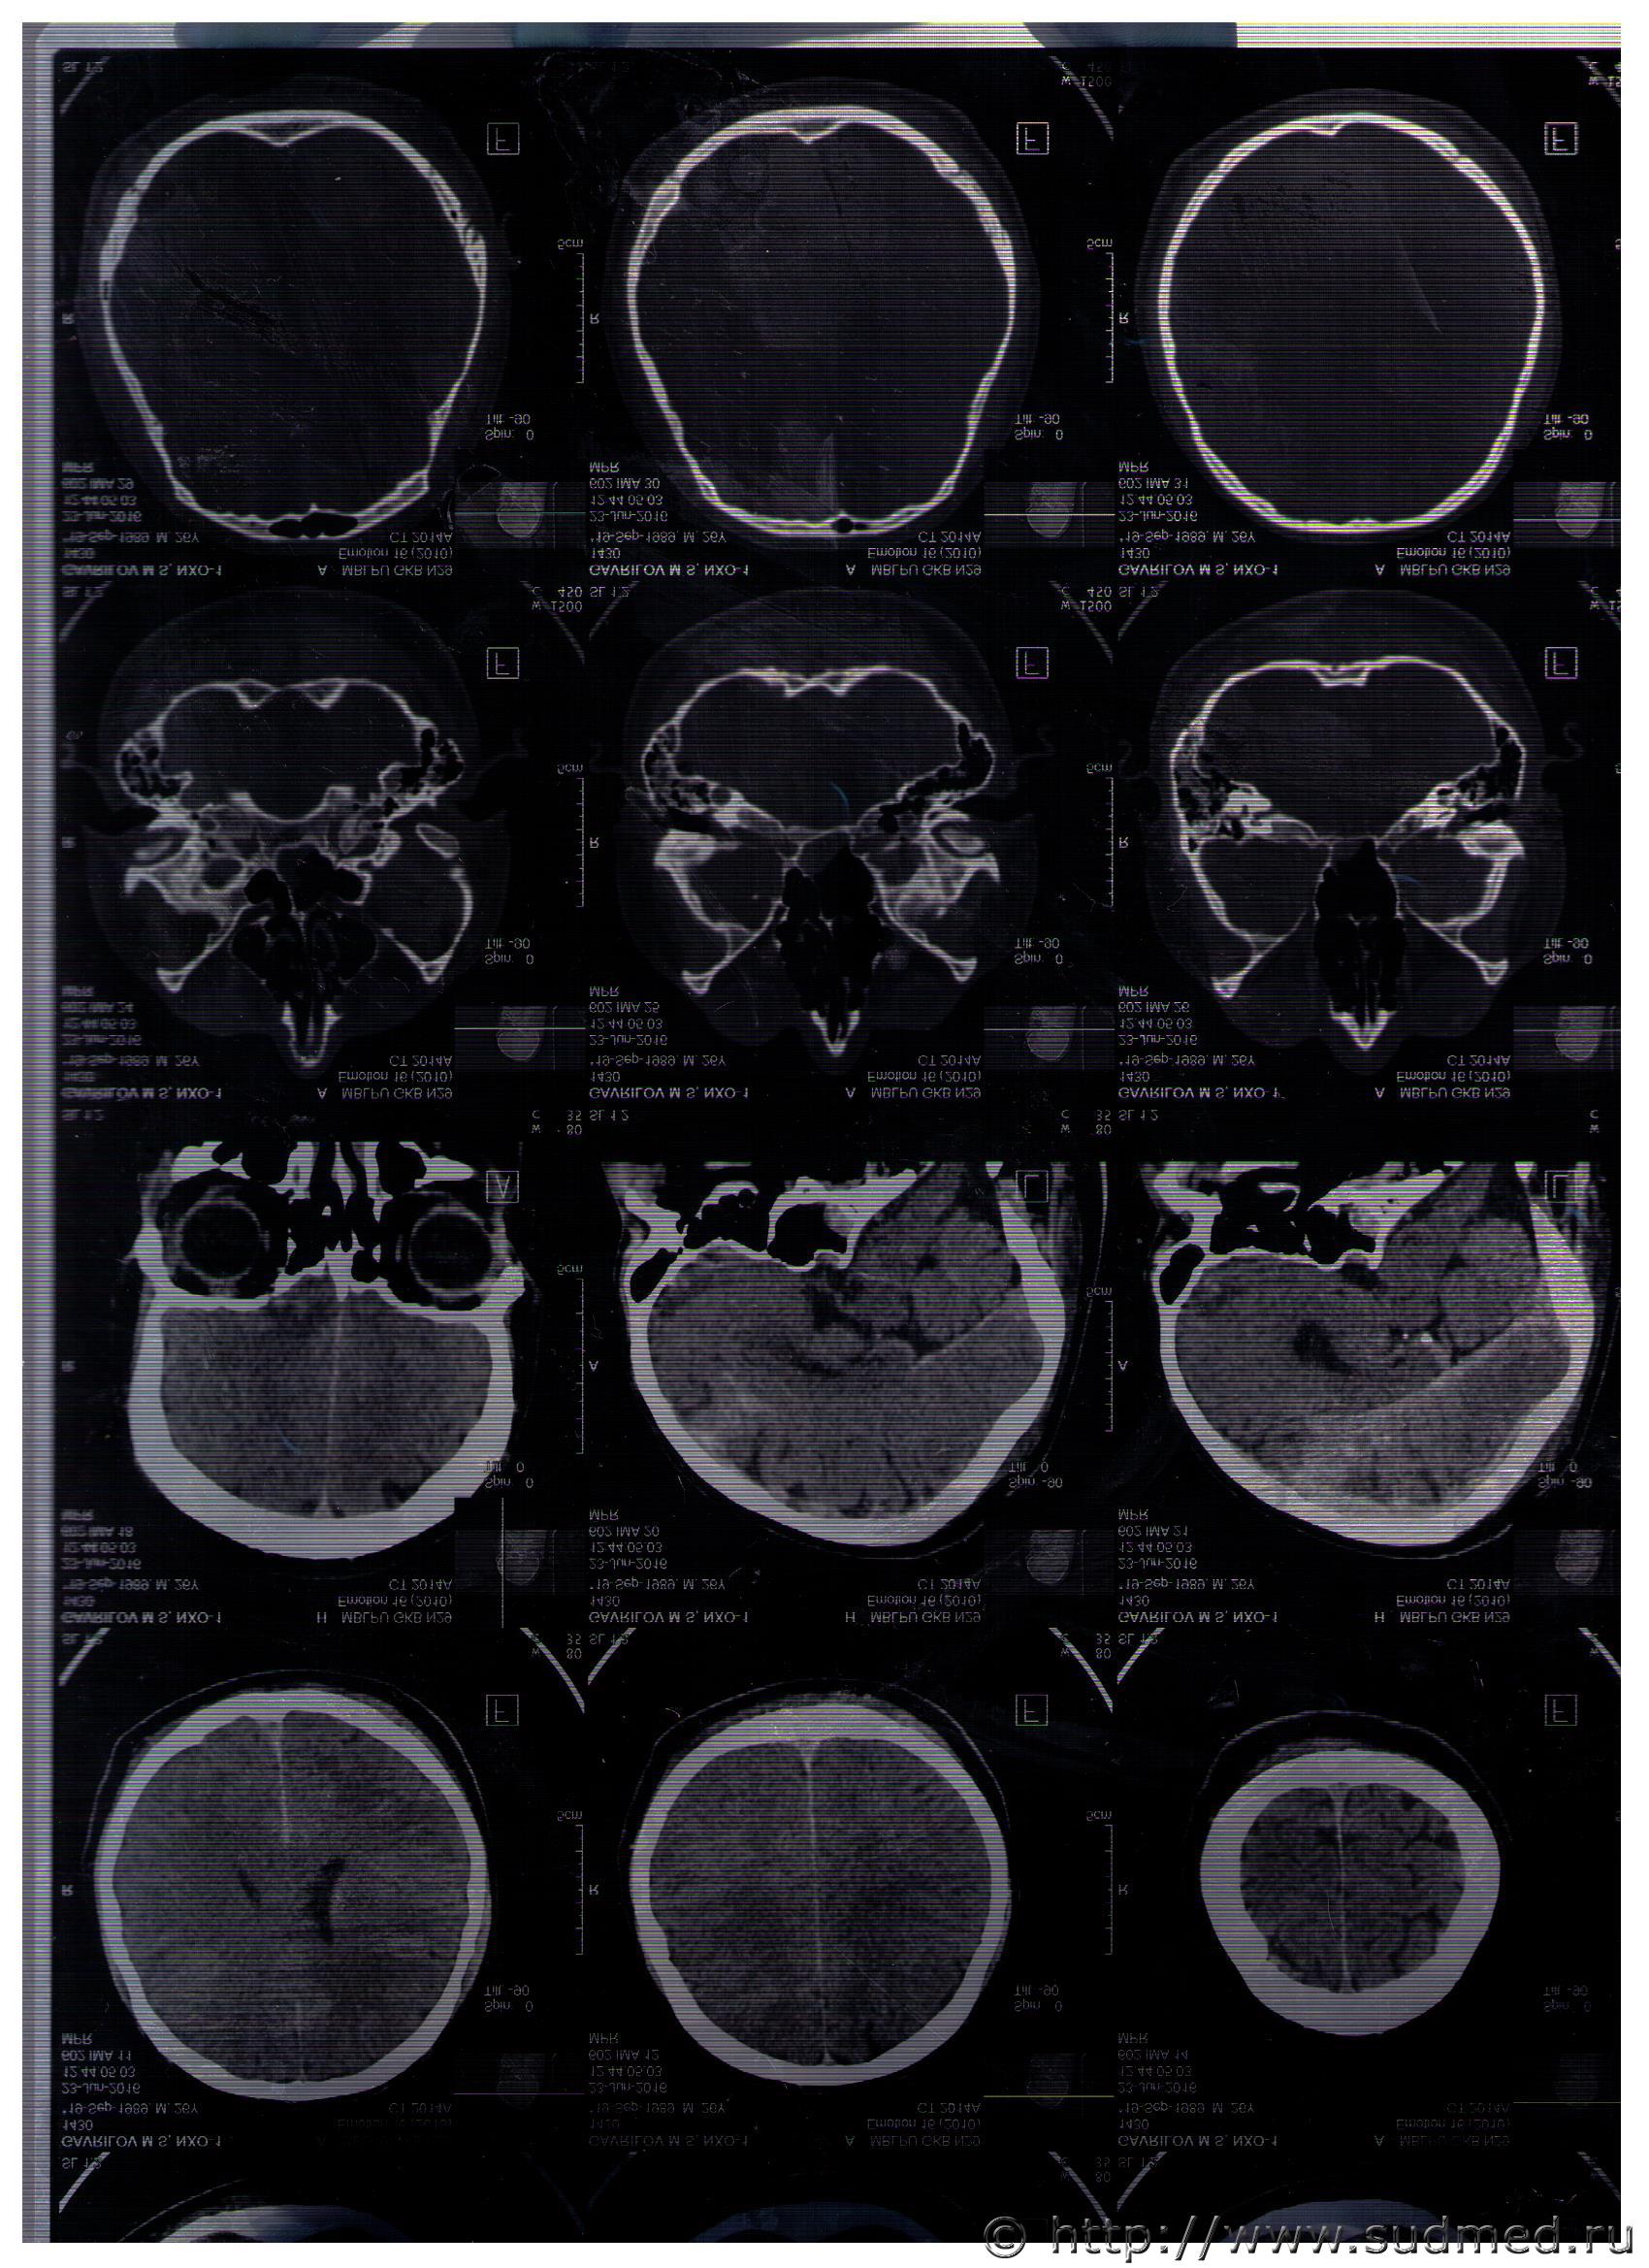

Судебная медицина - Прикрепленное изображение

Перелома не видно. Возможно, что из-за оч.заметной потерия качества изображения при сканировании и электронной передаче снимков.

Обычно на пленке распечатывается несколько десятков сканов, при том, что их выполняется от полутора до трех-пяти сотен. Рекомендую взять ВСЕ сканы ВСЕХ КТ в цифровом виде (на CD или флешке) из КТ-архива (в костном режиме - ВСЕ строго обязательно!) и проконсультировать их у высококвалифицированного рентгенолога. Как я уже писал Вам ранее, появится значительно больше информации, в т.ч. возможность эффективно работать с изображениями, строить реформации в необходимых проекциях и т.д.